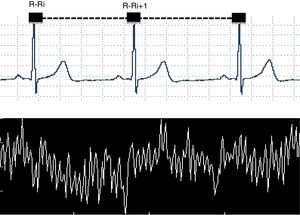

Heart rate variability (HRV), a non-invasive method used to evaluate the autonomic nervous system modulation on the cardiac sinus node,1–4 describes the oscillations between consecutive electrocardiogram R-R intervals (R-Ri), Fig. 1.

Data acquisitionThe first step in the procedure prior to HRV analysis is to determine the R-R interval time series, which can be done using various devices. In this context, aspects related to the devices used, the data acquisition rate, software used, time of registration and simultaneous data collection of various signals should be considered.